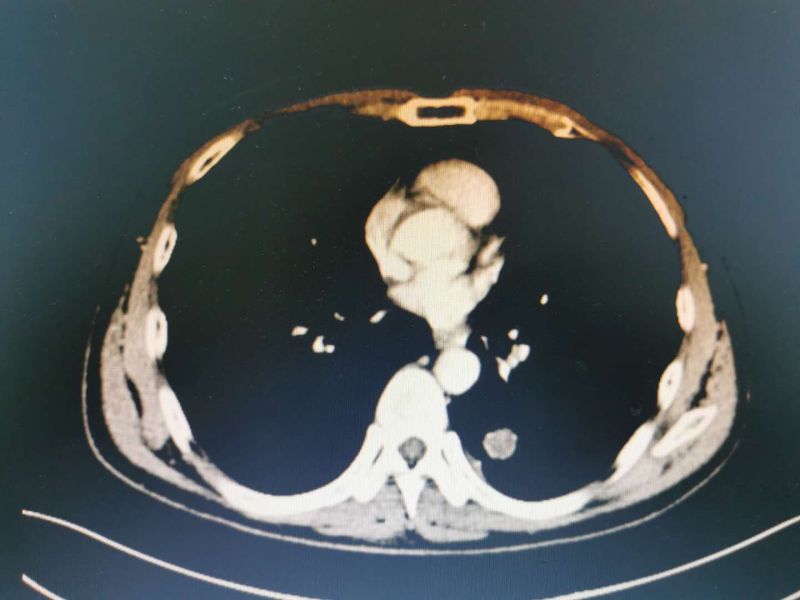

患者男性,51岁,因“反复胸闷”入我院心血管内科住院治疗,完善检查发下左下肺占位,经我科医师会诊后考虑“左下肺占位:恶性肿瘤可能性大”建议积极手术治疗。转入我科后予积极完善术前检查,经充分术前准备及术前讨论评估后在黄勇科主任为首的心胸外科团队努力下成功实施了单操作孔VATS下左下肺叶切除术并进行了系统淋巴结清扫,手术非常顺利,出血甚微。

患者CT影像学表现